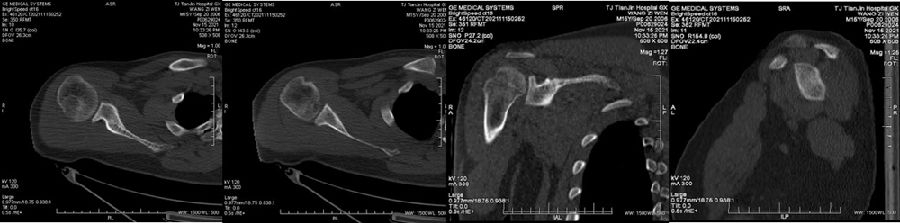

典型病例,苏X,男,36岁。主诉左肩关节反复脱位2年。诊断左肩复发性脱位、左肩胛盂骨折(骨性Bankart损伤)、左肱骨头Hill-Sachs损伤。

手术方案:左肩关节镜下探查清理、Latarjet术。

图45 CT D=26mm d=8mm(上患侧,下健侧)

图46 CT d/D=30.7% GT=0.83D-d=13.6mm Hill-Sachs损伤I级,骨缺损 >25%